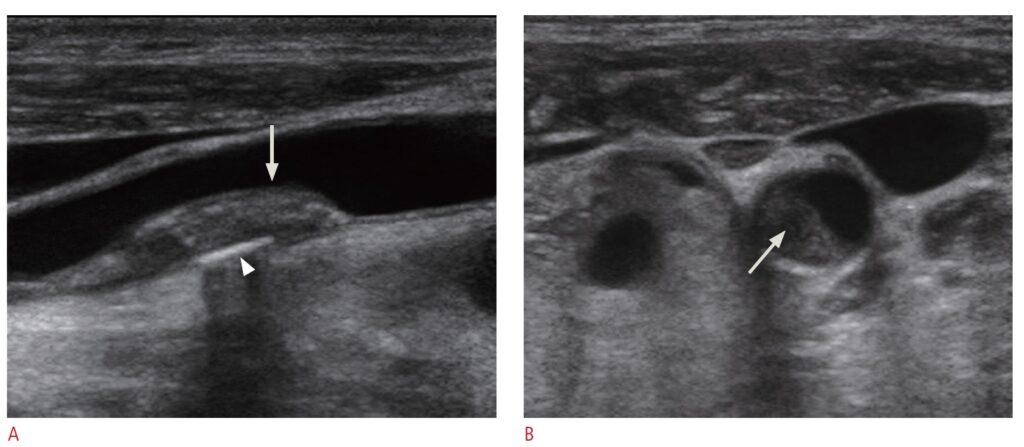

🩺 1. İntima–Media Kalınlığı (İMK)

- Damar duvarının kalınlığı değerlendirilir.

- Erken ateroskleroz (damar sertliği) bulguları araştırılır.

- Kardiyovasküler riskin dolaylı göstergesi olarak kullanılır.

🩺 2. Plak Varlığı

- Şah damarlarında plak olup olmadığı kontrol edilir.

- Mevcut plakların yerleşimi belirlenir.

- Genel görünümü ve yaygınlığı incelenir.

🩺 3. Damar Lümeni Hakkında Genel Değerlendirme

- Belirgin bir daralma şüphesi olup olmadığına bakılır.

- Kan akımının serbest olup olmadığına dair genel gözlem yapılır.